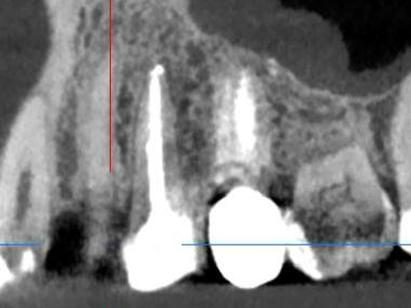

Лечение: Проведено перелечивание корневых каналов под микроскопом с удалением ранее внесённых материалов, тщательной механической и медикаментозной обработкой каналов и их последующей герметичной обтурацией. После лечения каналов выполнено восстановление коронковой части зуба.

После завершения эндодонтического лечения и стабилизации состояния зуба врач-ортопед провёл подготовку зуба под протезирование. Изготовлена и зафиксирована коронка. (Фото 2 и 3).

Результат: Болевые ощущения при накусывании полностью устранены, дискомфорт при жевании отсутствует. Зуб сохранён и полноценно восстановлен. После установки керамической коронки восстановлены анатомическая форма и жевательная функция.